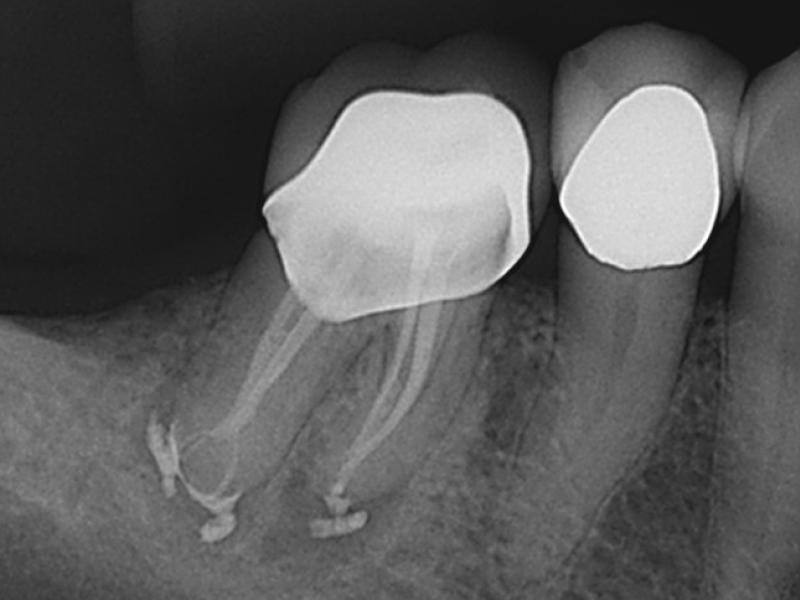

Recall